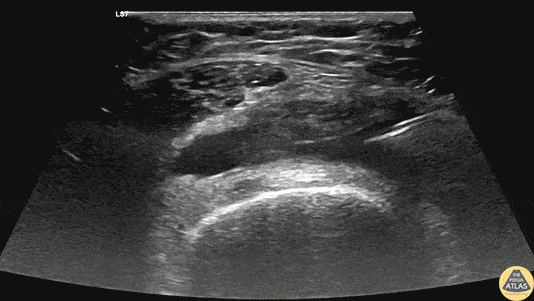

40s F with prior history of contralateral trimalleolar ankle fracture s/p multiple surgeries presents 1 month of knee swelling and pain after starting levofloxacin. The symptomatic knee appeared swollen without warmth or erythema, ROM was preserved, and the patient was ambulatory. Point of care US demonstrated an effusion around the knee, so diagnostic and therapeutic arthrocentesis was performed as shown here. The linear probe was used in a transverse orientation just superior to the patella to view the suprapatellar bursa just deep to the quadriceps tendon. Using sterile technique, a needle was advanced under real-time, in-plane US guidance to enter the bursa and aspirate synovial fluid. Ultimately the patient did not have septic arthritis and was discharged with a compressive knee wrap with a plan for orthopedic surgery follow up. Dr. Caleb Knight, PGY-2 Denver Health Residency in Emergency Medicine